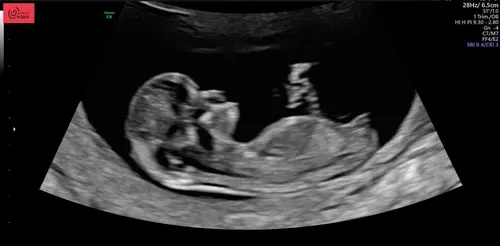

14 weken

Kan iemand er iets van maken? Echo bij 12 + 6

Vandaag precies 13 weken en de echo gehad! Al willen wij het tot het einde niet weten wat het wordt, ben ik toch benieuwd wat jullie denken te zien! ☺️ Gewoon voor later om te zien of het klopte 😉

Hier 13+2, iemand een idee? 🩵🩷

Iemand idee 13+5 🥰